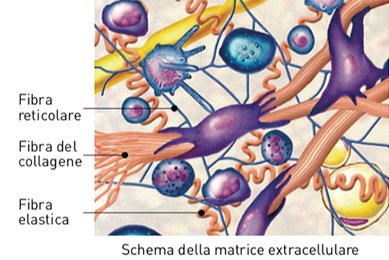

È la proteina più presente nel corpo umano, circa il 30% di quelle totali. Forma la struttura dei tessuti dell’apparato locomotore (cartilagini, ossa, legamenti, fasce), dei tessuti di protezione e supporto (pelle e tessuto connettivo), dei tessuti con funzione specifica (pareti dei vasi sanguigni e linfatici, cornea, cuoio capelluto, gengive, dentina).

Il collagene ha una struttura fibrosa, che apporta notevole resistenza e flessibilità ai tessuti, e ha una composizione che lo rende unico per l’elevato livello di aminoacidi glicina e prolina, e per le forme idrossilate di prolina e lisina, che non si trovano in nessun altro tipo di proteina.

Le eliche si uniscono tramite i loro estremi costituendo una catena più lunga (tropocollagene) e queste catene si raggruppano poi in parallelo per formare le microfibre, che si uniscono formando le fibre che danno poi origine a quelle di collagene. Questo cordone proteico spesso ma flessibile forma la matrice (rete tridimensionale o fasci di fibre) che costituisce la struttura del collagene.